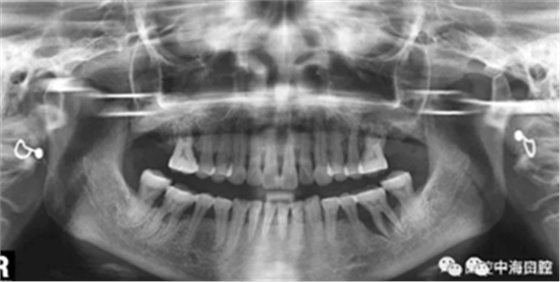

下面這兩張圖,據(jù)說拔牙費(fèi)時(shí)1.5小時(shí),收費(fèi)14000元。